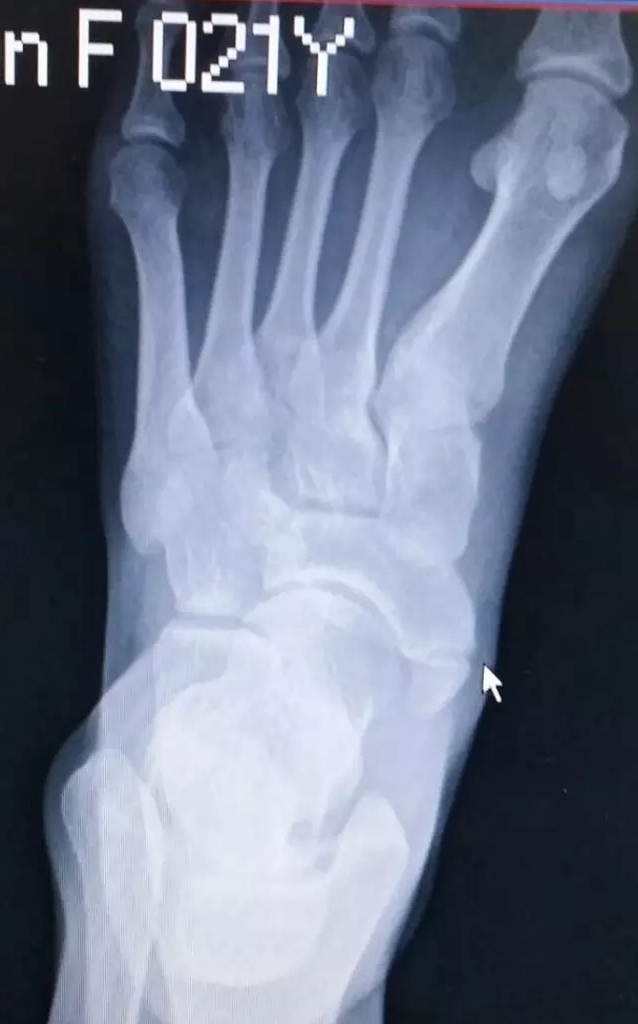

足副舟骨是发生在舟骨结节第二骨化中心的先天性变异。大约有10-15%的人会存在足副舟骨。

足副舟骨是人体最大的副骨,可分为3型。

一型不与舟骨相连,一般无症状。

二型副舟骨是舟骨的一部分,由结节部纤维软骨板分开。进一步分为2A和2B型。

三型二者有骨桥连接,形成角状舟骨。

当发生足副舟骨疼痛时,首先要拍X光确诊,并确定分型。